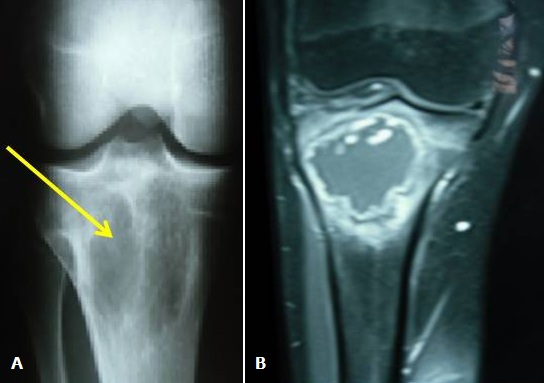

Le lymphome de Burkitt est un lymphome lymphoblastique B caractérisé par une prolifération monoclonale de cellules lymphoïdes B . L'atteinte osseuse au cours de ce type de lymphome est un événement rare. La localisation maxillo-faciale semble être la plus fréquente. Cependant l'atteinte des os long reste exceptionnelle. Nous rapportons une nouvelle observation d'un lymphome de Burkitt révélé par des gonalgies inflammatoires. IL s'agit d'un patient âgé de 17 ans, qui se plaint de gonalgie droite, d'allure inflammatoire évoluant depuis quelques mois. L'examen du genou ne montre pas de signes inflammatoires locaux, ni de limitation de la mobilité. La biologie trouve un SIB et une anémie à 9 g /dl. La radiographie standard du genou (A) montre la présence de lésions ostéolytiques métaphyso-épiphysaire de l'extrémité supérieure du tibia et l'imagerie par résonnance magnétique (B) une ostéolyse géographique ovalaire métaphyso-épiphysaire soufflante mesurant 59/53 cm siégeant au niveau de l'extrémité supérieure du tibia avec une zone de transition étroite qui se rehausse en péri-lésionnel sans rehaussement intra lésionnel après injection du gadolinium. La biopsie de cette lésion était non concluante et devant la survenue d'une hématémèse, une fibroscopie oeso-gastro-duodénale faite a conclu à la présence d'une antrite nodulaire et d'une lésion duodénale dont la biopsie a montré un lymphome de Burkitt. Le bilan d'extension a conclu à une atteinte ganglionnaire diffuse, pancréatique, rénale bilatérale et digestive. Le patient a été traité par chimiothérapie. L'évolution était favorable par la disparition des douleurs. Le scanner de contrôle a montré une régression des lésions osseuses (disparition des lésions tissulaires) avec début de reossification.